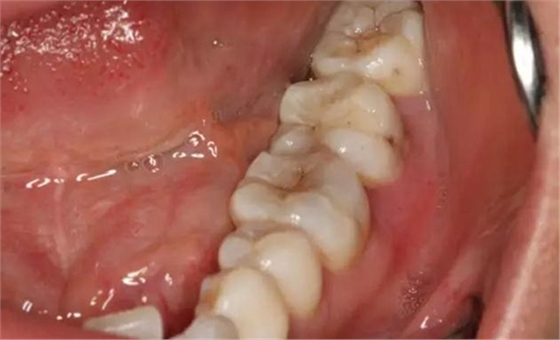

圖2. 37牙冠基本完好,松動Ⅰ度。合面有一開髓孔被棉球覆蓋,頰側(cè)牙齦輕度紅腫。